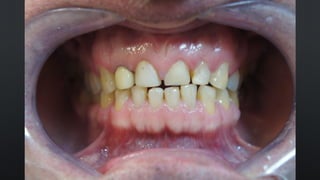

• OVERBITE OU SOBREMORDIDA

RELAÇÃO ENTRE ARCOS

TRESPASSE VERTICAL

• REFERE-SE AO QUANTO OS INCISIVOS SUPERIORES COBREM NOS INFERIORES

• APROXIMADAMENTE 30%

• OVERJET OU SOBRESALIÊNCIA

TRESPASSE HORIZONTAL

• REFERE-SE AO DISTANCIAMENTO ENTRE OS INCISIVOS SUPERIORES E INFERIORES

• NORMALMENTE 2MM

• OVERBITE OUSOBREMORDIDA RELAÇÃO ENTRE ARCOS TRESPASSE VERTICAL • REFERE-SE AO QUANTO OS INCISIVOS SUPERIORES COBREM NOS INFERIORES • APROXIMADAMENTE 30%

• OVERJET OUSOBRESALIÊNCIA RELAÇÃO ENTRE ARCOS TRESPASSE HORIZONTAL • REFERE-SE AO DISTANCIAMENTO ENTRE OS INCISIVOS SUPERIORES E INFERIORES • NORMALMENTE 2MM